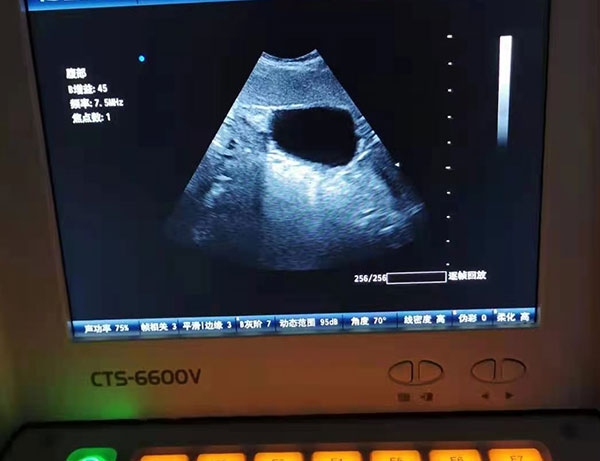

宠物是有其偏好的。我们的确遇到过在看诊时近男狂吠的特迪勒克,上一秒抓狂听到大夫的名字,突然就老实了田园猫大白了,还有来医院就像“回家”的金毛糖墩,只有大夫B超会乖乖的把腊肠卡放在一边……在动物医院里,经常可以看到这些“有个性”的猫狗。看诊的选择不仅仅取决于人,猫狗也会做出自己的选择。